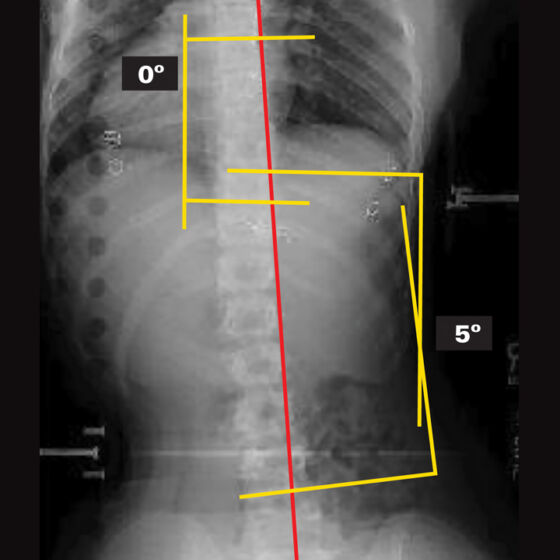

26° Right Thoracic, 26° Left Thoracolumbar Curve

25° Right Thoracic, 21° Left Lumbar Curve

45° Right Thoracic Curve

34° Right Thoracic, 30° Left Lumbar Curve